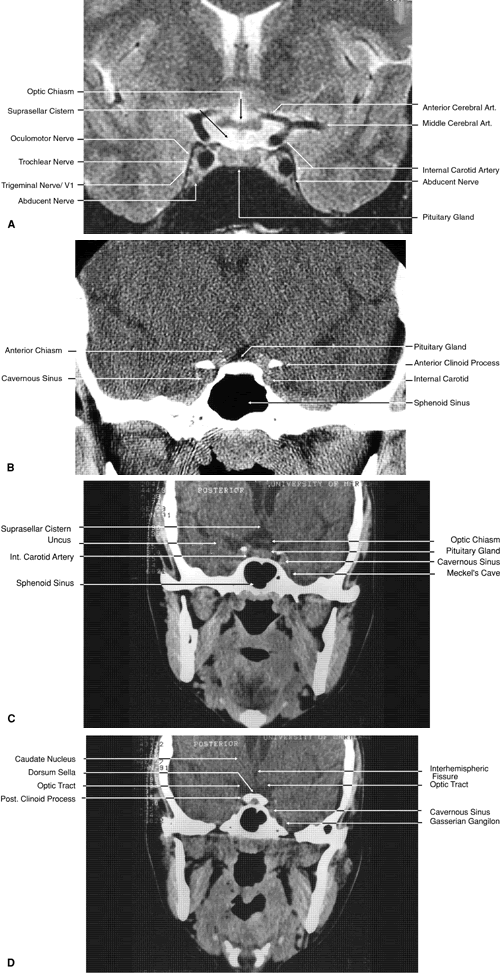

Fig. 27. Coronal images through cavernous sinus and optic chiasm. A. T1-weighted magnetic resonance imaging through anterior chiasm. B. Computed tomography image through anterior chiasm. C. Computed tomography image through posterior chiasm. D. Computed tomography image through optic tract.

Fig. 28. Axial computed tomography image with contrast medium through cavernous sinus and pituitary gland.